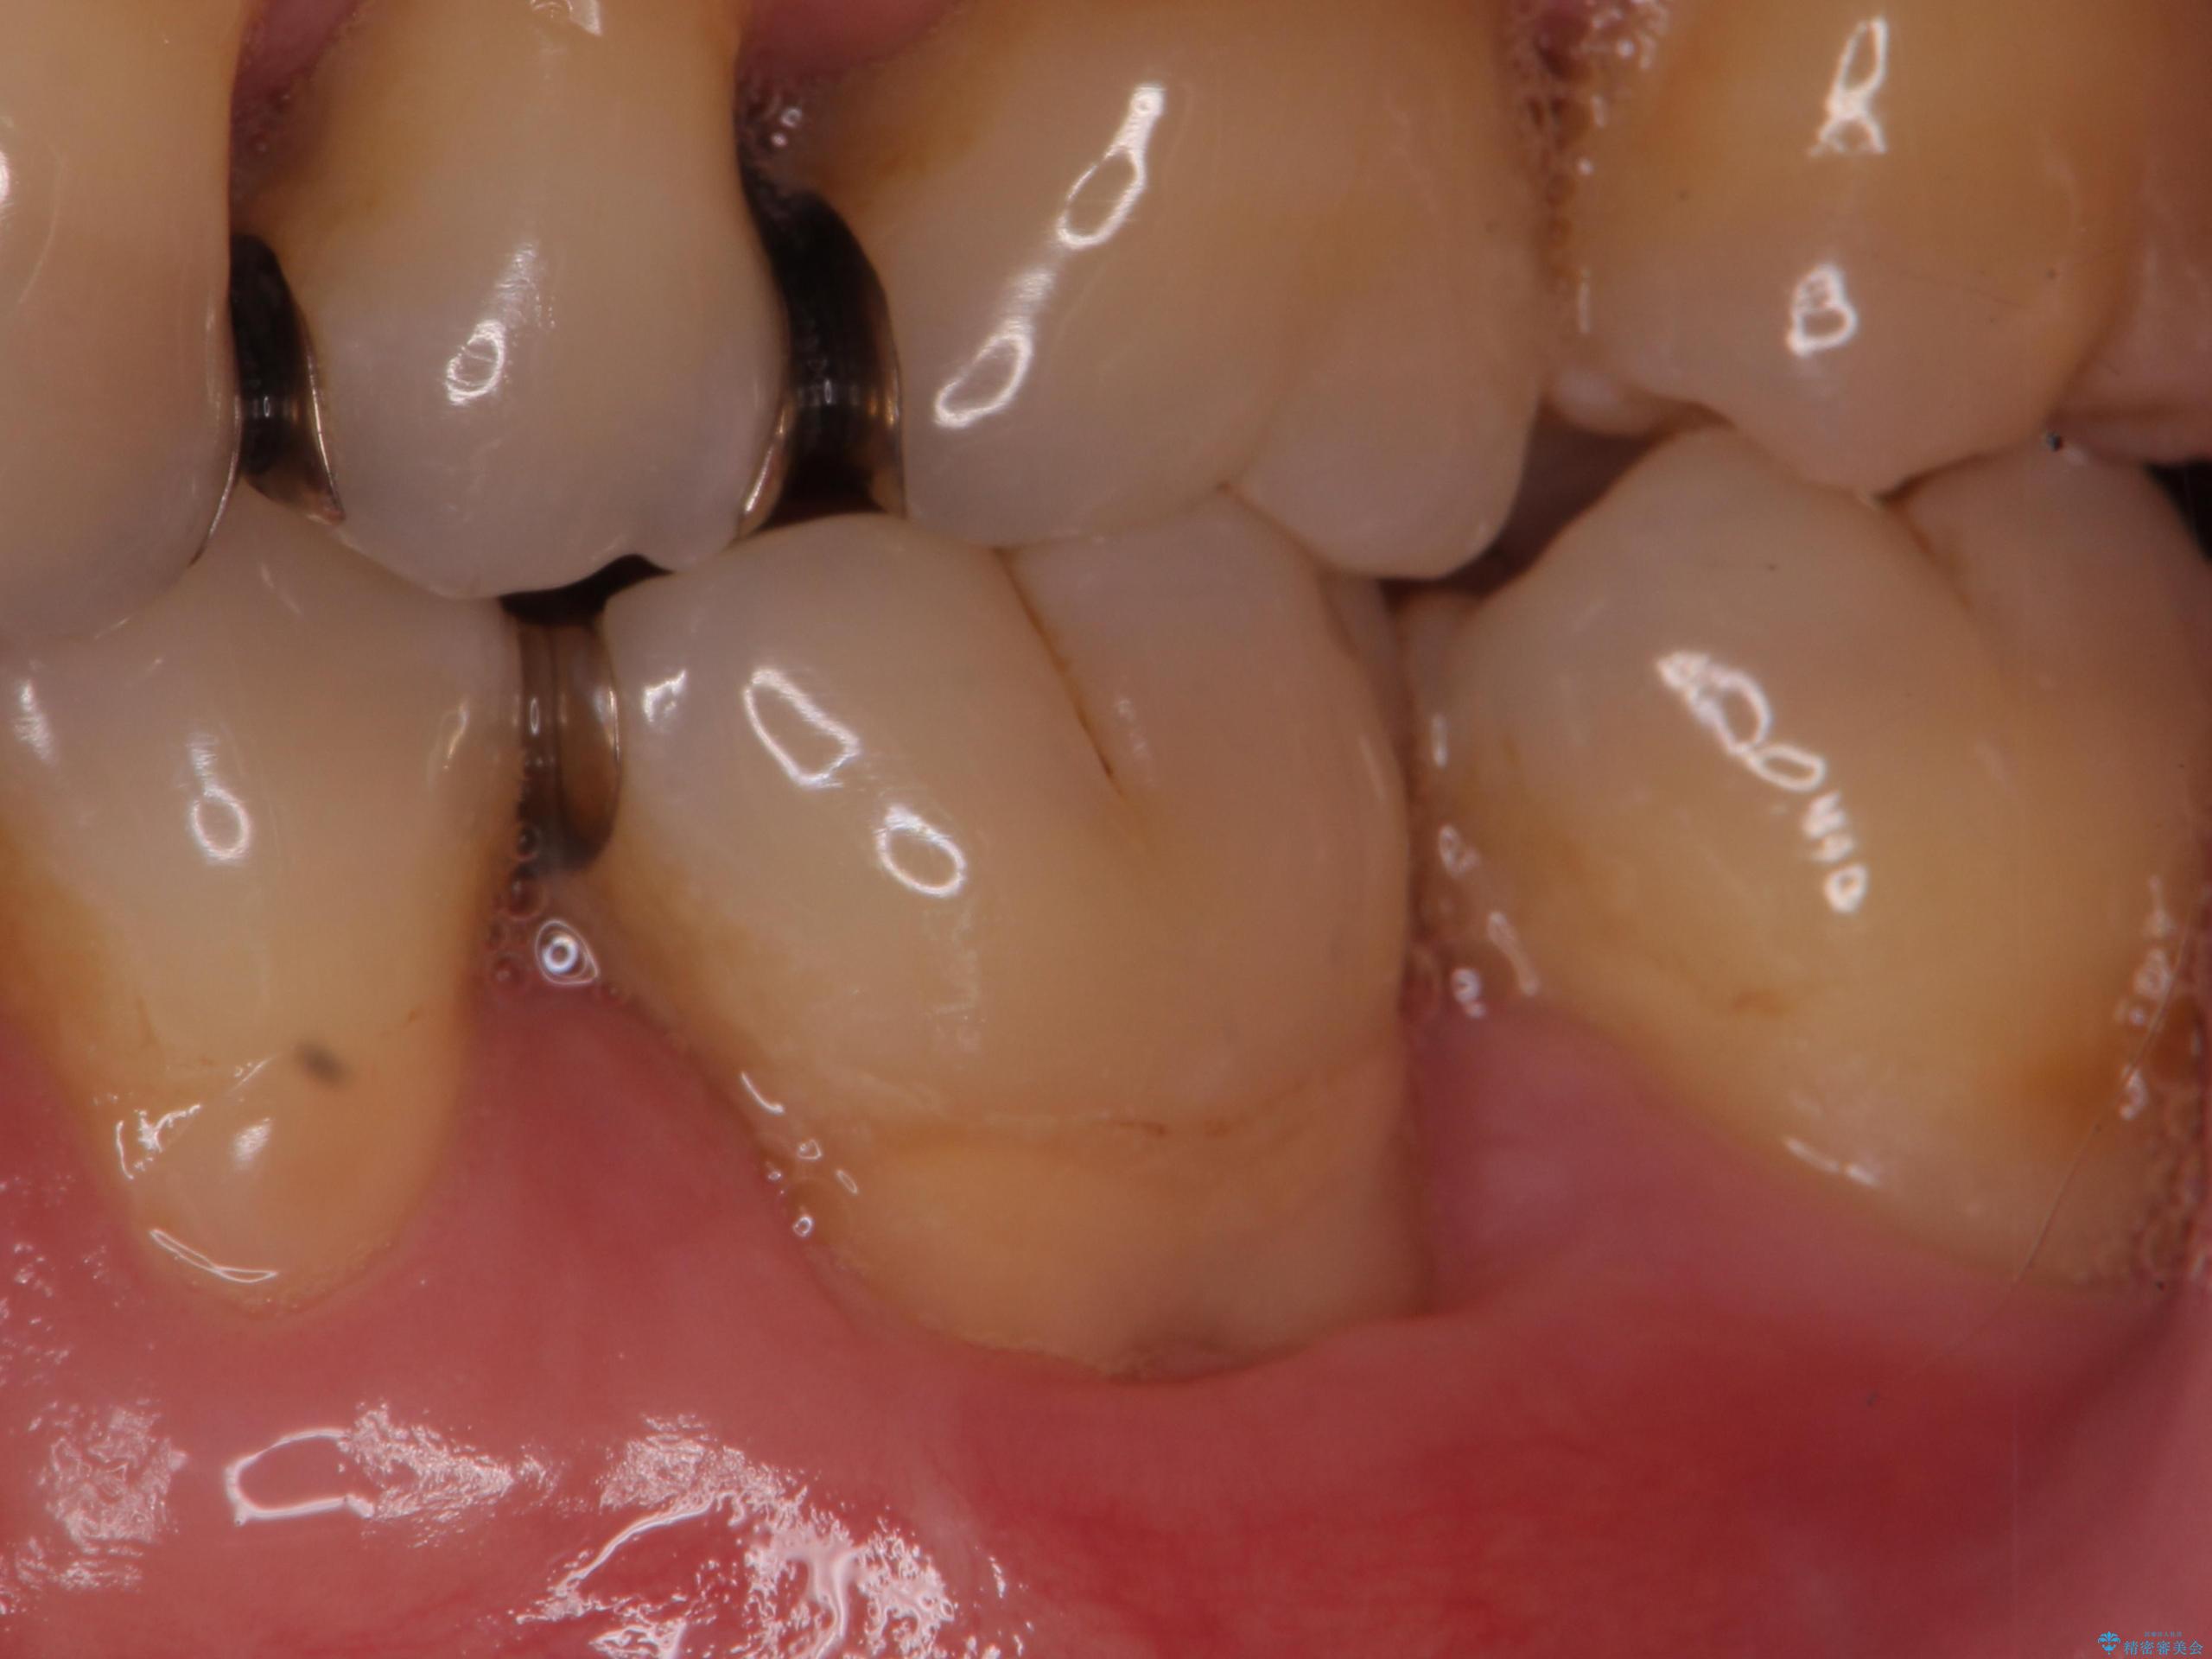

- 奥歯の歯茎が下がっていて(歯肉退縮)歯が染みるとのことで来院された患者様です。

退縮した歯茎に対して移植をすることで、しみる場所を覆う計画です。

歯根の分岐部よりも根尖側の頬側面が露出している状態でしたが、露出部位を分岐部までに抑えることができました。